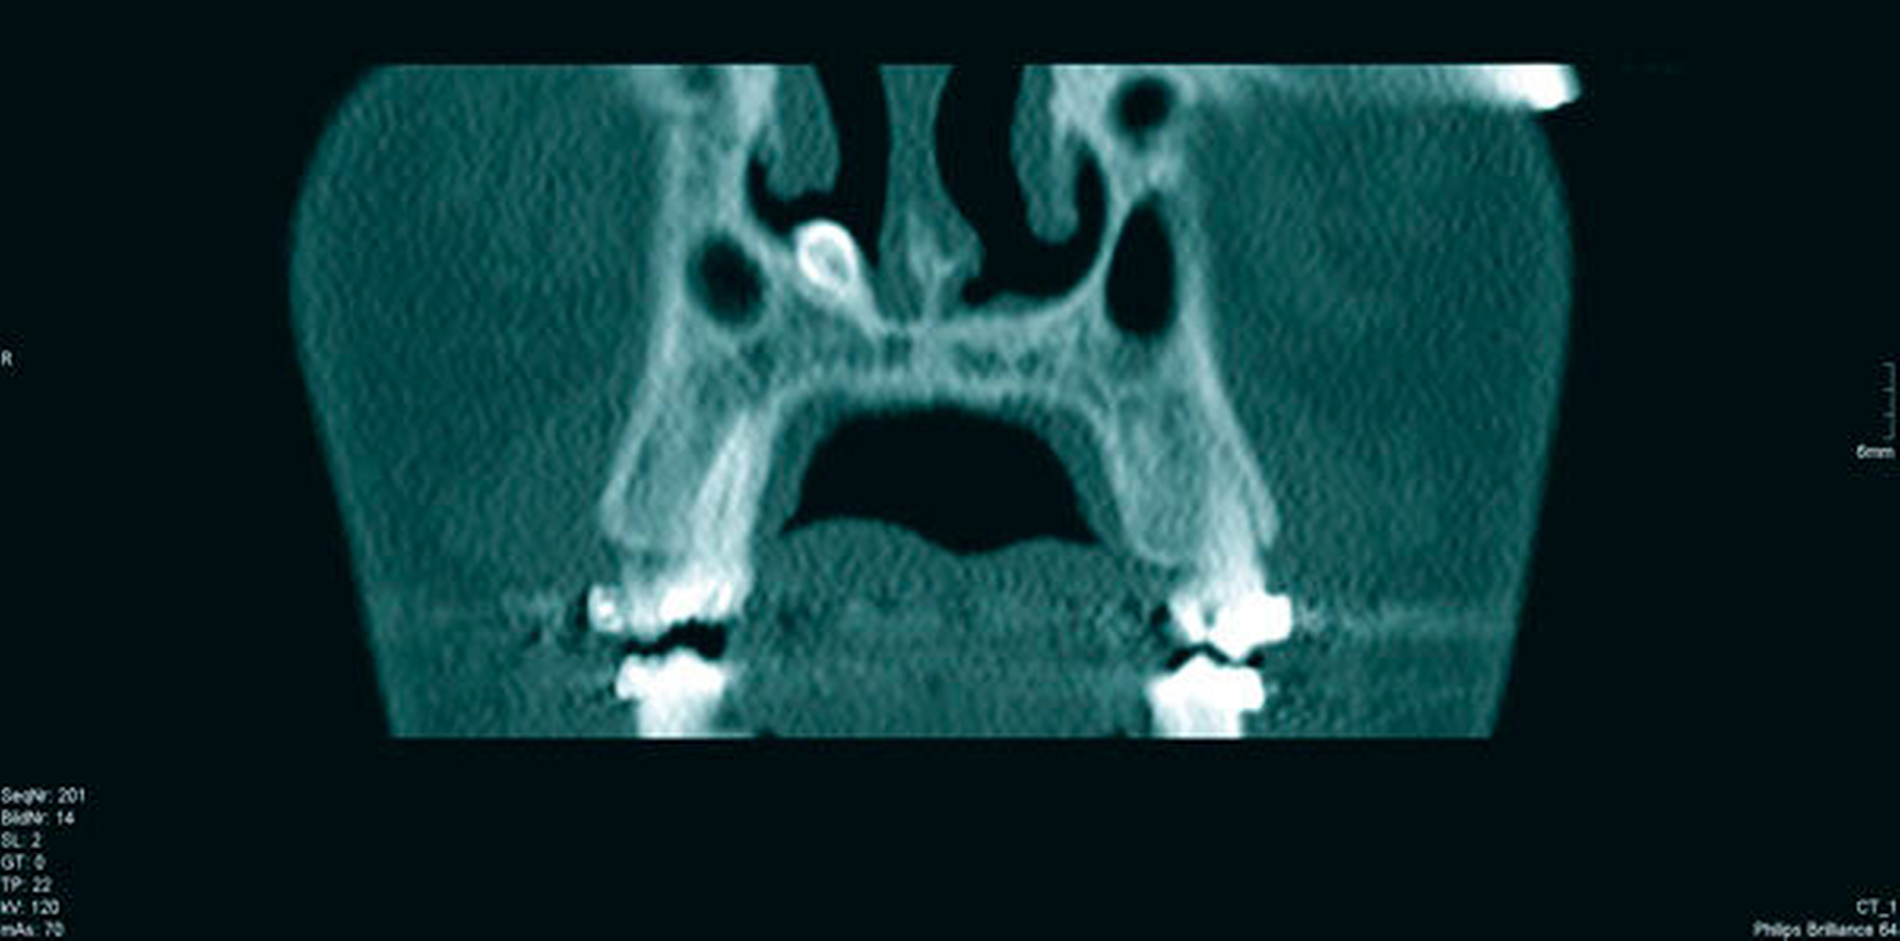

Das angefertigte OPT (Abbildung 1) zeigte einen ektopen, überzähligen Zahn 13a. Nach Komplettierung der Bildgebung durch eine Computertomografie (Abbildungen 2a und 2b) fand sich der Zahn kranial im rechten Nasenboden gelegen. Nebenbefundlich konnte eine polypöse Schleimhautschwellung der rechten Kieferhöhle festgestellt werden.

Acht Monate postoperativ lag bei der klinischen sowie radiologischen Kontrolle ein unauffälliger Befund vor. Das Verlaufs-OPT zeigte einen zeitgerechten Befund im rechten Oberkiefer nach Zahnentfernung und Kieferhöhlenrevision (Abbildung 4). Der Patient ist postoperativ nach wie vor beschwerdefrei. Weitere röntgenologische Verlaufsuntersuchungen sind nicht geplant.